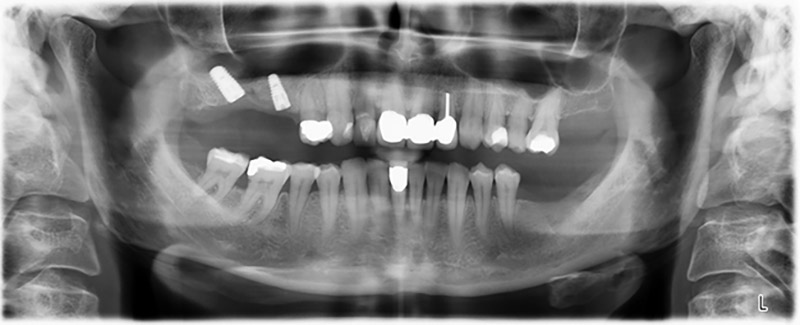

Orthopantomogramm

Abb. 20: Orthopantomogramm nach Behandlung